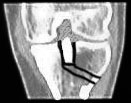

3. Die Ausführung: Am Schienbein werden diverse Schnitte vollzogen. Im Bild rechts oben (3) ist der Schnitt von vorne sichtbar, im rechten unteren Bild (4) ein Schnitt von oben. Aus dem Schienbein ein Keil entfernt, sodass die zuerst von überschüssigen Knochenfragmenten befreite Eminenz gewissermassen nach vorne und unten ins Schienbein geklappt werden und mit drei Schrauben festgemacht (5) werden kann. In den unteren beiden Bildern ist auch schön sichtbar, dass die Eminenz nun wieder eine normalere Form hat.

Schön sichtbar sind auch die alten Löcher der im November 2001 entfernten Schrauben sowie in den Bildern rechts (gelbe Pfeile) eine alte Unterlagsscheibe, die während dem Sommer 2001 im Knochen festgewachsen war und im November nicht herausgefischt werden konnte (auf die Bildfragmente klicken, um eine grössere Fassung des Ausschnittes zu sehen).

Die neue Konstruktion von vorne bei ca. 45° gebeugtem Knie. Rechts von der Eminenz ist einer der frischen Schnitte im Knochen sichtbar.